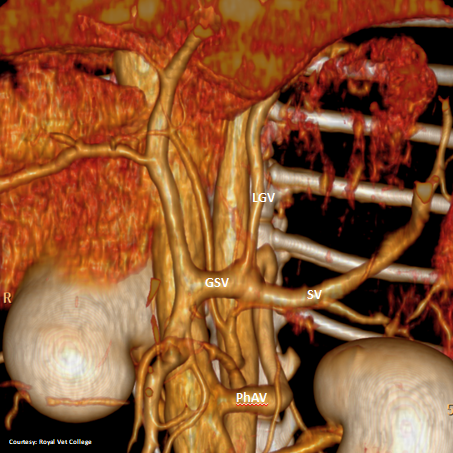

Does LEFT GASTRIC VEIN (LGV) enter the GASTROSPLENIC VEIN (GSV)?

WEISSE 2022

slide10